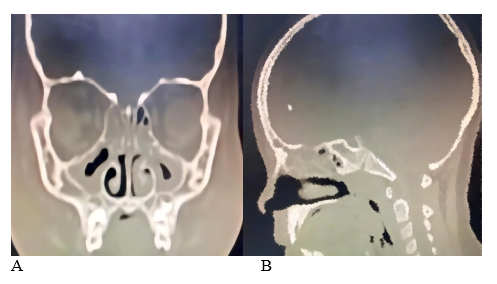

A 6-year-old female presented to the emergency department with a 72-hour history of fever and swelling of the right eyelid. Previous outpatient antibiotic treatment had failed (amoxicillin and ceftriaxone). Physical examination revealed periorbital erythema and edema, without any restriction of extraocular movements. Nasal endoscopy showed significant turbinate enlargement (inferior and middle) and purulent discharge from the right middle meatus. Laboratory results indicated a high white blood cell count (18.0 K/mm³) with a neutrophilic predominance (82%). The patient was admitted for intravenous antibiotics (meropenem, vancomycin) and steroid therapy. A CT scan of the paranasal sinuses revealed opacification of the frontal, ethmoid, and maxillary sinuses, with sphenoid mucosal inflammation. There was also obstruction of the osteomeatal complex, hypertrophy of the inferior and medial turbinates, and enlargement of the adenoids (Figure 1); there were no signs of intracranial extension. Based on these findings, a diagnosis of pansinusitis complicated by preseptal cellulitis was established.

Figure 1 CT scans (A; coronal, B; sagittal) show increased opacity in the frontal, ethmoid, maxillary, and sphenoid regions, along with blockage of the osteomeatal complex and enlargement of the adenoid.